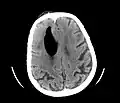

| Pneumocephalus and comminuted fracture of the frontal sinus |

Pneumocephalus is the presence of air or gas within the cranial cavity. It is usually associated with disruption of the skull: after head and facial trauma, tumors of the skull base, after neurosurgery or otorhinolaryngology, and rarely, spontaneously. Pneumocephalus can occur in scuba diving, but is very rare in this context.